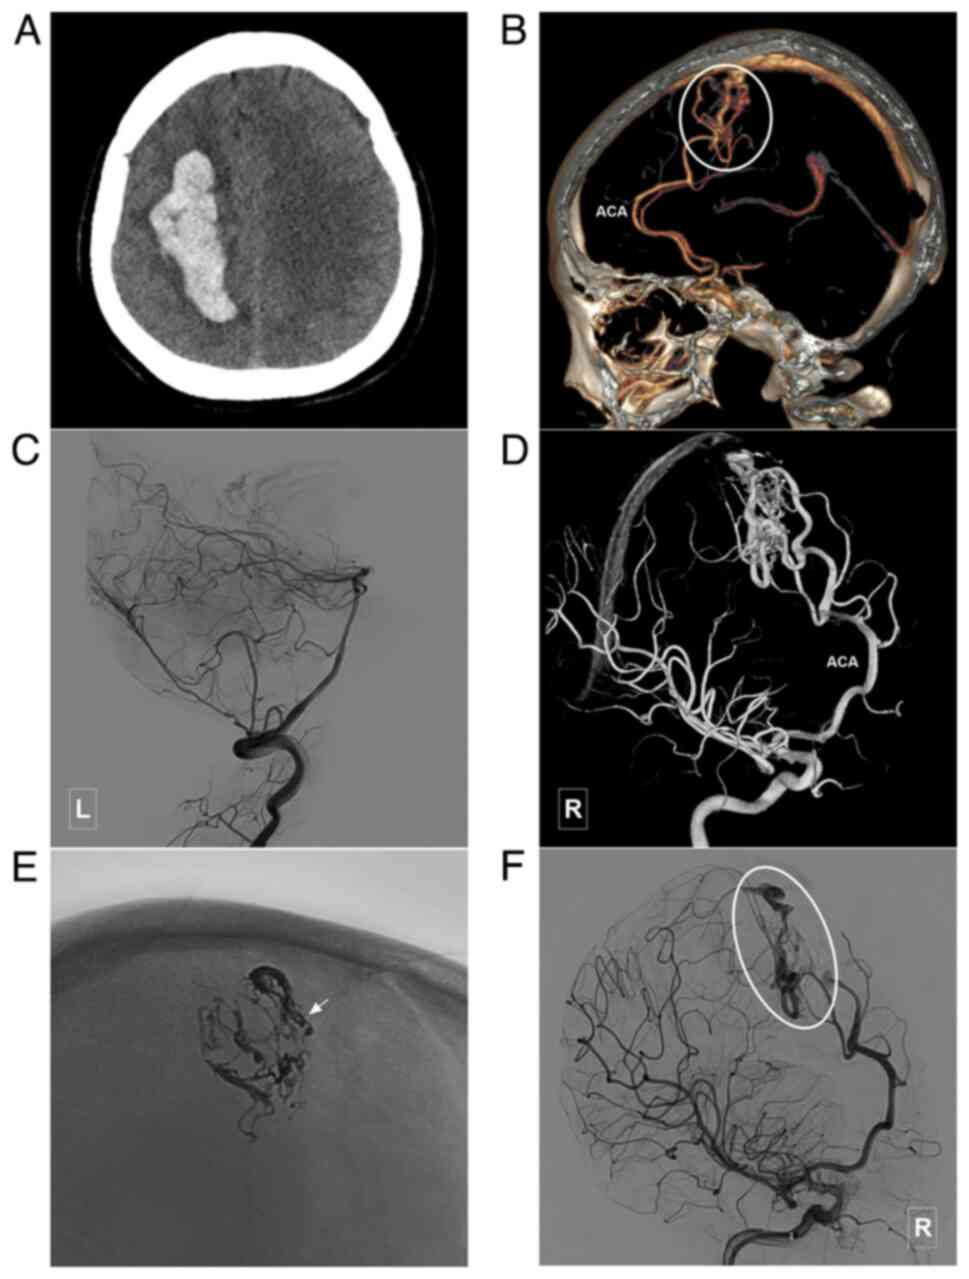

Figure 6

Typical case of a type III BAVM. (A) Head CT scan illustrating a hematoma located in the right fronto-parietal lobe. (B) Head CTA illustrating a BAVM (encircled area) supplied the A4-A5 segment of ACA and drained to the sagittal sinus. (C) Angiogram of the left vertebral artery illustrating that the posterior circulation is not involved in the blood supply of the BAVM. (D) Three-dimensional angiogram of the right internal carotid artery illustrating that the terminal branch of the ACA is involved in the blood supply of the BAVM. (E) X-ray of the cranium illustrating Onyx casting. The arrow denotes the coils in the feeding artery near the nidus, and the ‘pressure cooker’ technique (before Onyx casting, the coiling was performed to occlude the feeding artery to prevent Onyx reflux) is used during treatment. (F) Angiogram of the right internal carotid artery following treatment illustrating that the BAVM is almost completely embolized, while the draining veins (encircled area) remains. ACA, anterior cerebral artery; BAVM, brain arteriovenous malformation; CT, computed tomography; CTA, computed tomography angiography; L, left; R, right.